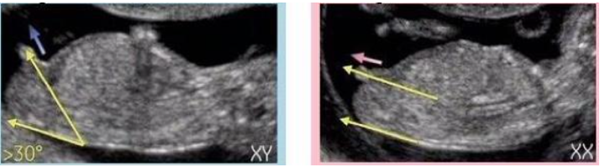

男孩的特征点与身体呈45度角,还多一些,而女孩儿的特征点几乎和躯体平行。还有就是如果是男宝宝,屁股位置会微微上翘,后背脊柱成圆弧状,因为要留空间发育前列腺,相反,女宝宝后背脊柱就相对就平一些,如下图所示: